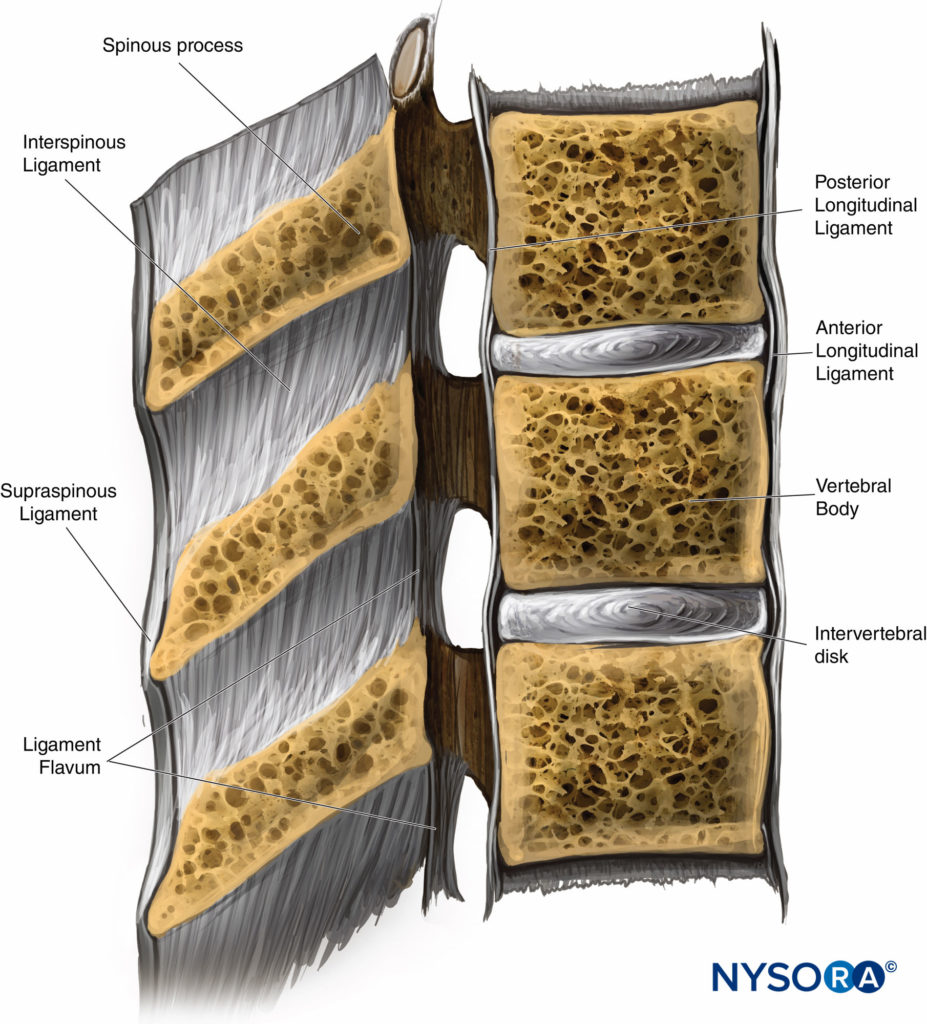

Pure Health - Anatomy 101 - Supraspinous ligament and interspinous ligament 📚 The supraspinous ligament and interspinous ligament work together to limit flexion of the spine by limiting separation of the spinous

DOCS - The interspinous ligament is located between the spinous processes of adjacent vertebrae in the spine. It extends from the base of one spinous process to the apex of the next,

Anatomy of the vertebral column and spinal cord (Chapter 55) - Essential Clinical Anesthesia Review